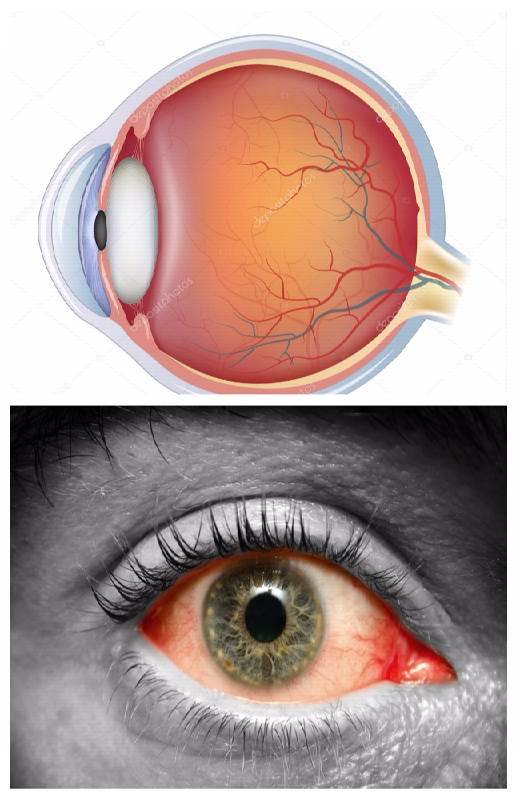

Изображения и анатомия сетчатки глаза